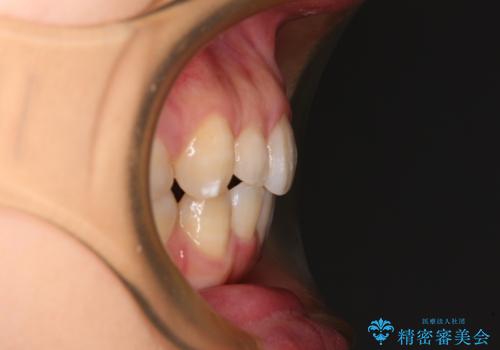

抜歯矯正の後戻り インビザライン・ライトによる矯正治療

- 矯正治療の後戻りを気にして来院された患者様です。

後戻りは軽微であったので、インビザライン・ライトにより矯正治療を行うこととしました。